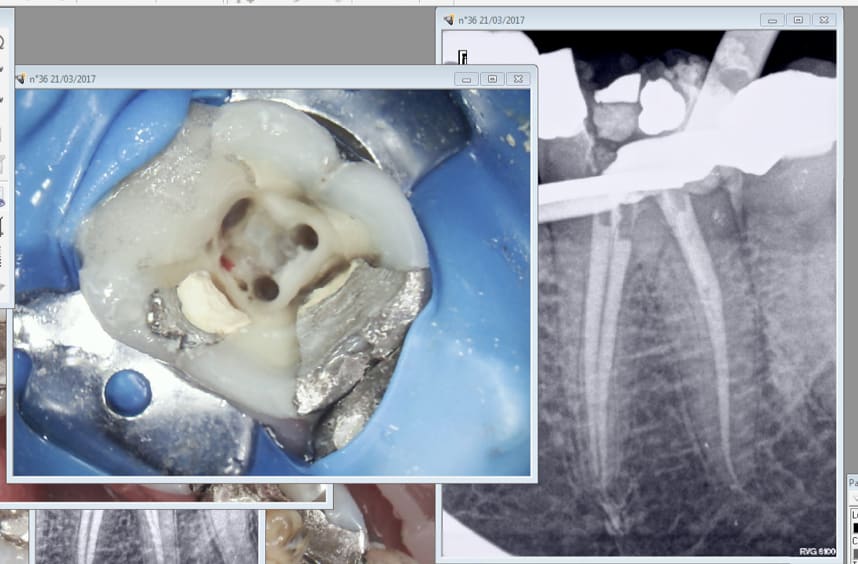

Tiens encore une pour la route. -)

Qu'est-ce qui saigne en lingual ?

J'ai pensé la même chose, le "tiens encore une pour la route", quoi une perf ? :D

Peut-être un bout de saucisson pour lardon ? Ou une contre dépouille avec un peu de pulpe ?

Exact. -)

Putain ca marche du tonnerre de dieu le joypex 5. je suis plus rapide qu'avec l'endomaster. -)

faut être sérieux chicot ; tu juges sur une radio en 2d effilée l image d'une dent en 3d . Si au moins on avait des radios selon différents angles ce serait mieux!!!!voir mémé une 3d , et tu verrais que le cone n 'est peut être pas si centrale que ça mais plus en vestibulaire avec une fausse route !

Probleme de topographie:

on a tizot qui a demandé tres justement:

"Qu'est-ce qui saigne en lingual ?"

On a dcs qui dit:

"oir mémé une 3d , et tu verrais que le cone n 'est peut être pas si centrale que ça mais plus en vestibulaire avec une fausse route !"

Est ce qu'avec la photo de chicot et le petit machin rouge non identifié (un peu vif pour du sang mais bon, les photos....), on a un moyen de savoir si c'est une 36 (la fausse route serait en lingual?) ou une 46 (ca serait en vestibulaire).